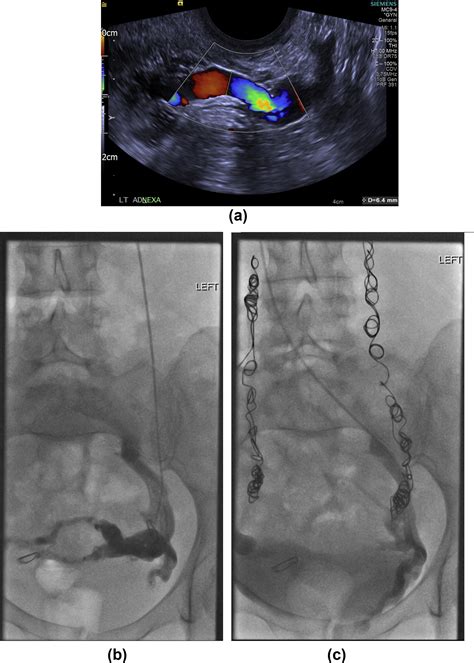

• Imaging tests: Various imaging tests may be used to visualize the veins and assess blood flow. These tests include:

Doppler ultrasound Uses sound waves to create images of the veins and measure blood flow.

Venography Involves injecting a contrast dye into the veins to visualize them on X-ray images.

These tests help healthcare providers identify the location and extent of venous insufficiency and plan appropriate treatment.

• Embolization: A procedure where a catheter is used to insert a small coil or plug into the affected vein to block blood flow and redirect it to healthier veins.

• Sclerotherapy: Injection of a solution into the affected vein to cause it to collapse and seal shut.